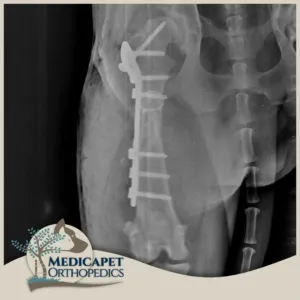

Eksternal Fiksatörler

Bazı kırıklarda kemiğe içeriden müdahale etmek uygun olmayabilir. Bu sebeple kırığı dışarıdan ya da çok küçük bir kesinin içinden redükte ettikten sonra vücudun dış kısmına yerleştirdiğimiz sabitleyici mekanizmalar ile sabit tutmayı amaçlayan ameliyatlar yaparız. Eksternal fiksatör kullanımı kesinlikle iyi bir biyomekanik araştırması ve tecrübesi gerektirir. Çünkü hastamız kırık uzvunu kullanmaya başladığında oluşacak gerilim ve yük bu fiksatörler üzerine binecektir. Bu sebeple yerleştirilecek olan fiksatörün konumu, yönü ve kemiğe göre pozisyonu büyük önem taşır. Biz klinik eksternal fiksatör uygulamalarımızda genellikle İlizarov sirküler monoblok ve her iki tekniğin kombine şekilde uygulandığı teknikleri başarıyla kullanıyoruz. Eksternal fiksatörler en çok, çok parçalı kırıklarda kullanılmaktadır. Bazı parçalı kırıklar içeriden müdahale edilirse eskisinden daha kötü hale gelebilirler. Bu sebeple kas doku bütünlüğünü bozmadan, mevcut kasların kırılan kemiğe desteğini sağlamak için insizyonsuz ya da minimal invaziv girişimlerde bulunuyoruz.